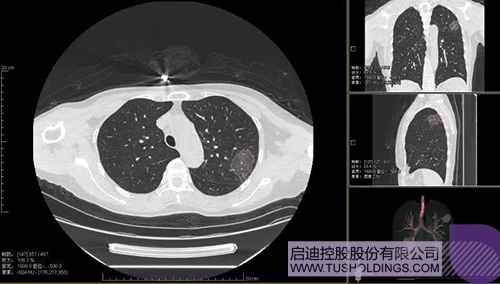

2020年2月11日,jjb科服投资企业—神州德信推出新冠肺炎检测及量化智能分析系统,积极助力一线医务人员科学精准防疫。